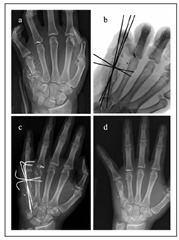

文献1】より

(a) 銃撃による第5中手骨骨幹部の粉砕骨折の術前X線写真。 (b) 非観血的整復および経皮的ピンニング後の術中透視像、および(c, d) 術後3週および23週のX線写真。骨折の癒合が進行し、骨のアライメントも良好である。